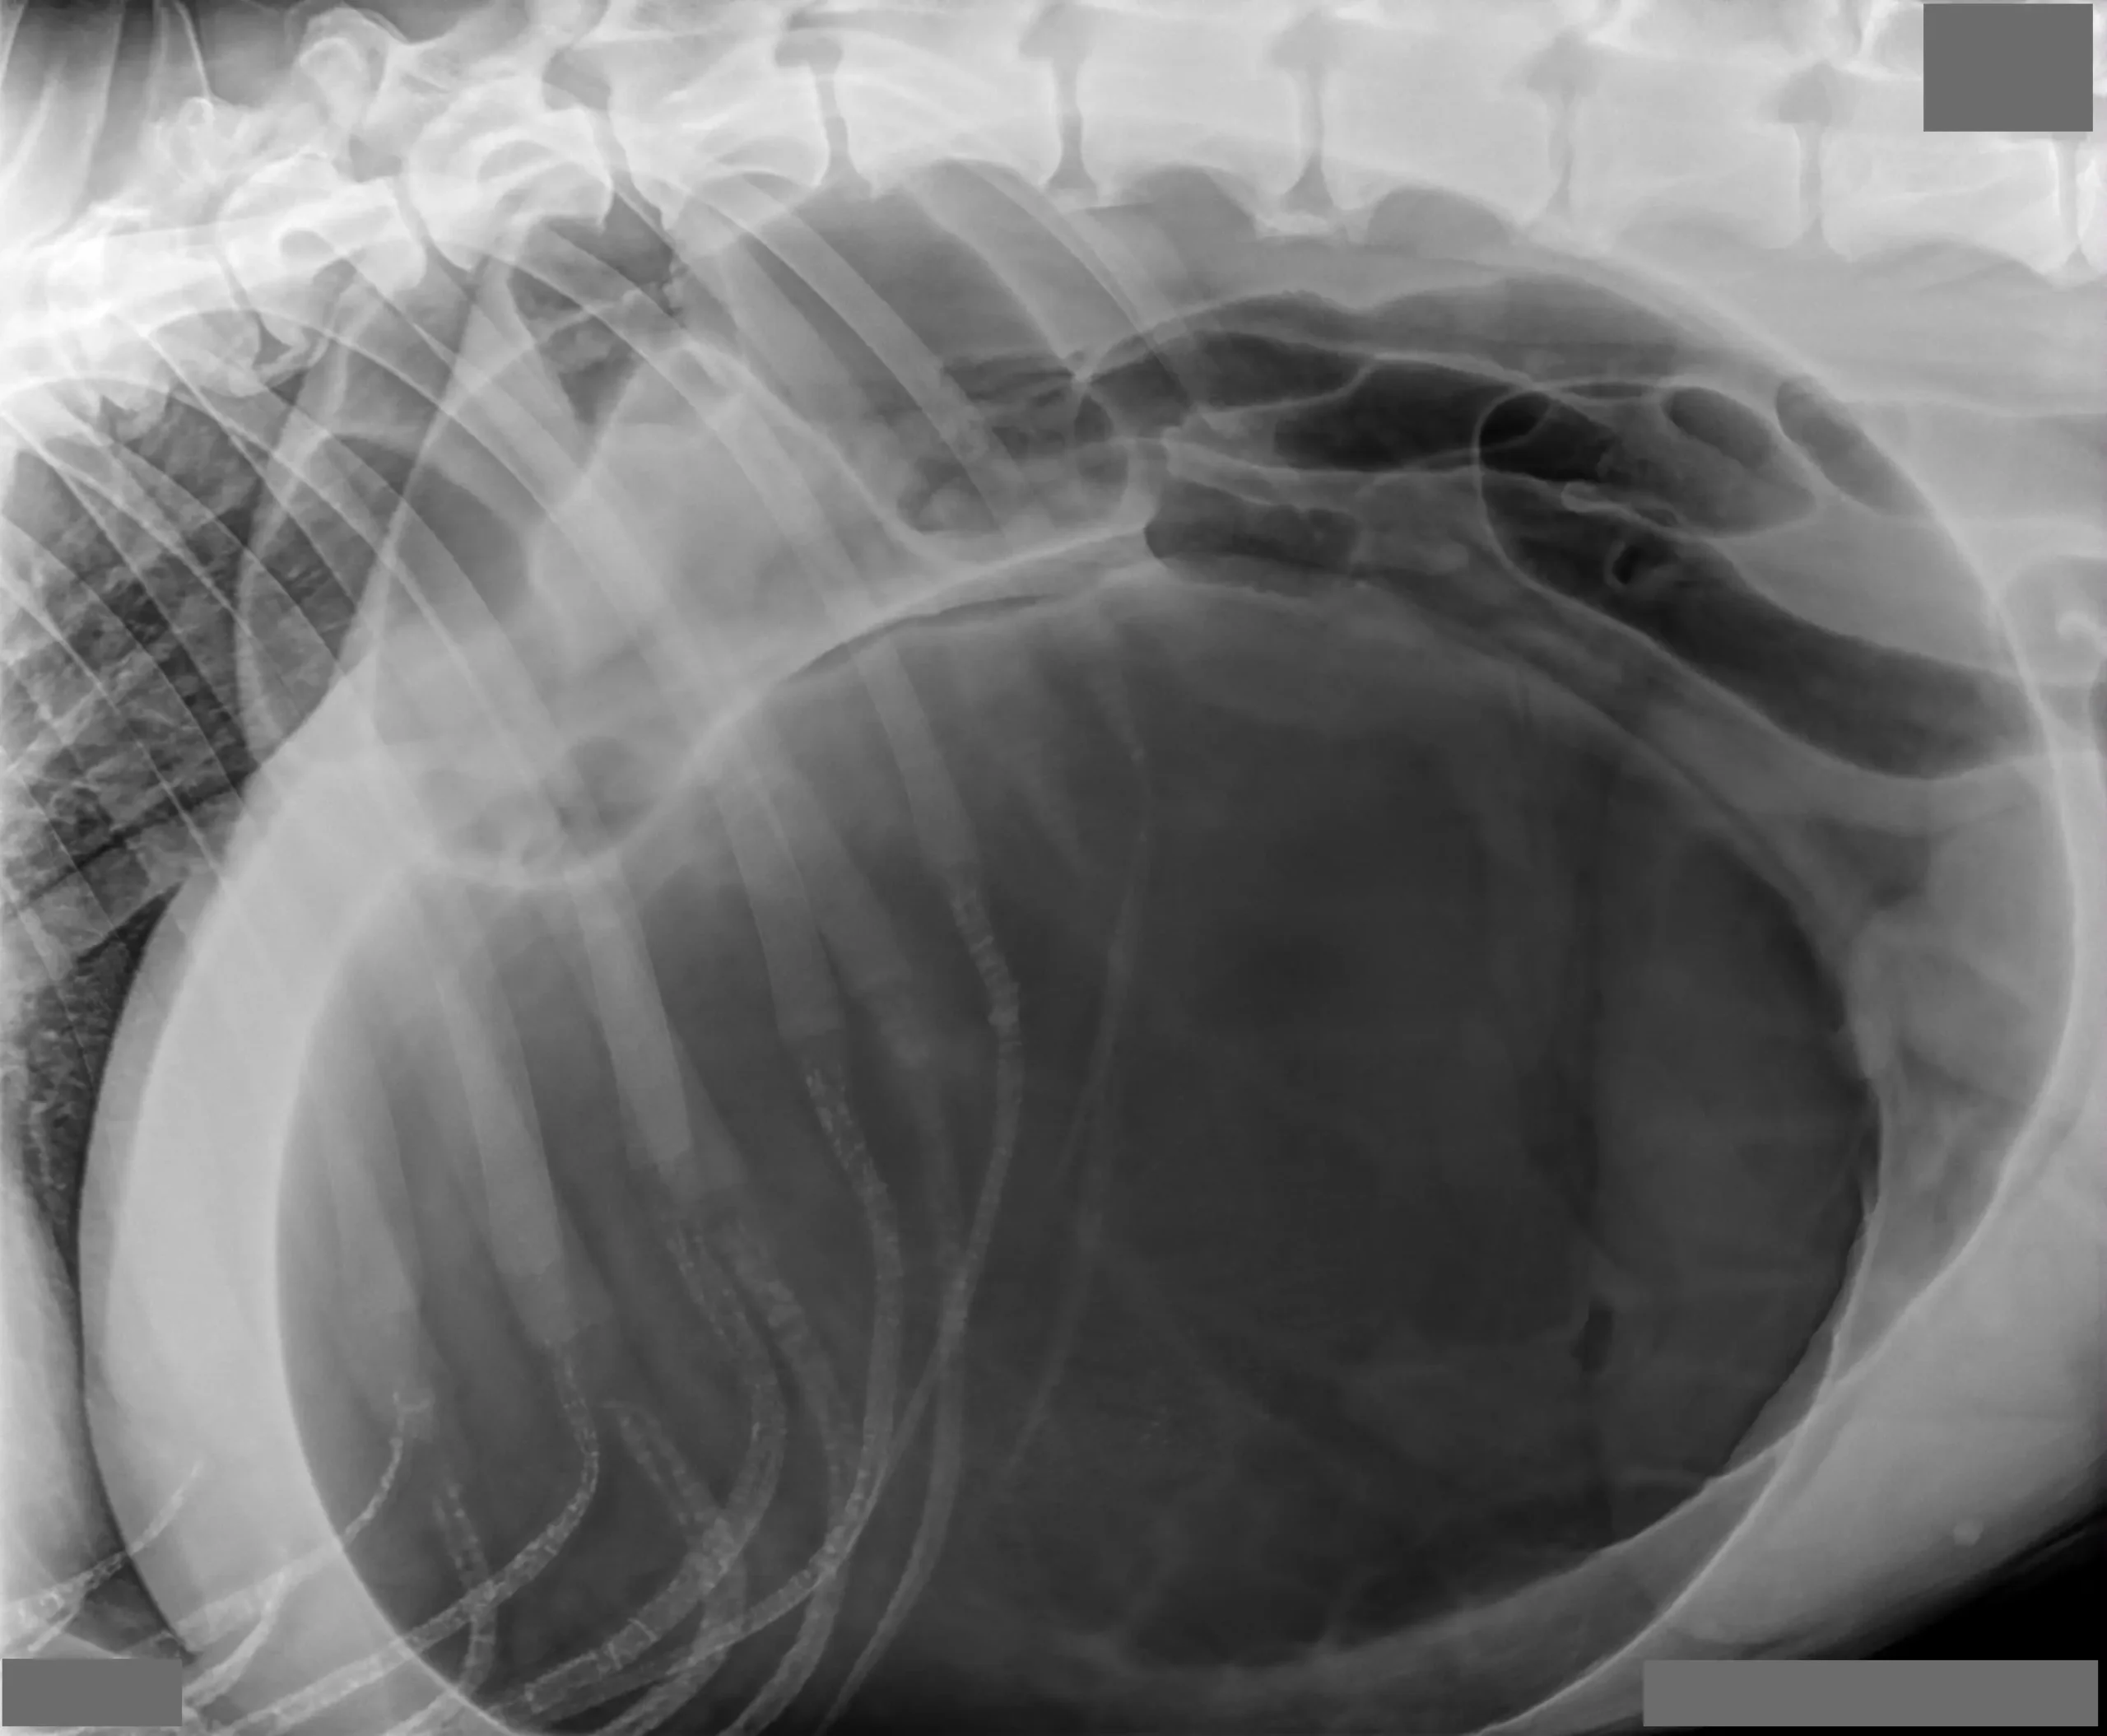

Gastric dilation and volvulus (GDV) or “bloat”, is a life-threatening condition that requires emergency surgery, and even with surgery, can result in death. The stomach twists in a clockwise direction as it becomes distended. The inlet to the stomach from the esophagus and the outlet leading into the duodenum get kinked off and the food, fluids, and air cannot pass in either direction. As a result, unproductive retching occurs. This is one of the more common symptoms of GDV.

Due to the twisting and displacement of the stomach, the blood supply may be cut off and a portion or all of the stomach may die. The longer that the stomach has been twisted before treatment is provided, the greater the risk that the stomach will die.

Another event that occurs is occlusion of the main vein (vena cava) leading from the back half of the body to the heart and resultant shock. Shock, a condition in which there is inadequate perfusion of the body with blood, is fatal if not treated. Signs of shock include pale gums, rapid heart rate, and weak pulses (low blood pressure). Dogs that develop GDV generally are quite ill and need immediate aggressive treatment. Emergency decompression of the stomach and surgical tacking of the stomach to the body wall is necessary